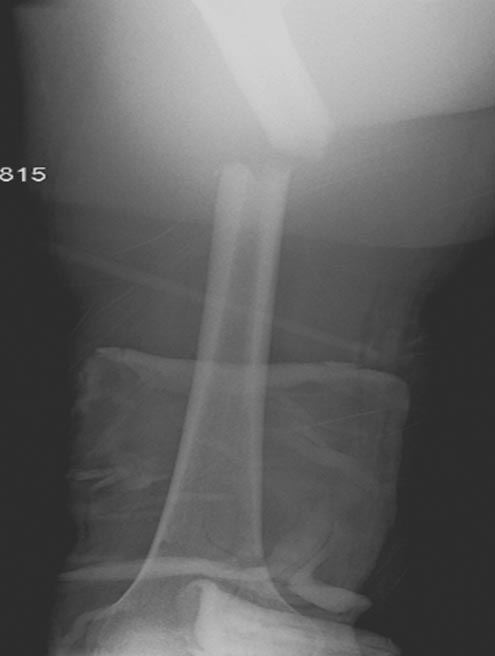

Травма хирург принял решение продолжать лечение в операционной. Срочная диагностическая лапаротомия с абдоминальной тампонадой, переливание 5 единиц крови. Irrigation & Debridement открытых ран с вакуумированием, попытка закрытой репозиции деформации сустава. По-прежнему состояние тяжелое, но давление стало стабилизироваться. Смогли получить первые диагностические данные.

Здесь перечислены ортопедические повреждения: Rt. femoral shaft fracture, Rt femoral head fracture-dislocation, Rt distal femur fracture, Rt. open patella fracture, Rt. talus fracture dislocation, Rt. open humerus fracture, Left 5th metatarsal fracture, Left dislocation 1st TMT.

6 день госпитализации-операция на таранной кости.

На 9й день фиксация дистального бедра, где фрагмент Hoffa и вертикальный перелом надколенника, зафиксированы винтами.